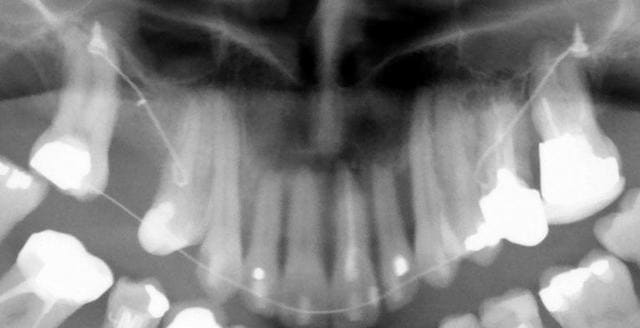

Mon cher alhoun, je ne pense pas que ce que tu dis soit entièrement exact, car je crois que la dent est sortie de l’os, poussée par les incisives inférieures et que le parodonte initial n’a pas complètement disparu. A distinguer d’une perte osseuse totale liée à un problème bactérien. On peut d’ailleurs voir sur la pano l’empreinte de l’apex sur l’os.

Si on trace mentalement sur le téléprofil une ligne représentant le mouvement global espéré en direction haute et distale, on constate qu’elle passe par la crête infra-zygomatique (voir la radio que je te mets sur la planche photo).

La traction s’effectue en direction de la crête infra-zygomatique, donc vers le haut, donc réalise à la fois un recul et une ingression (voir le téléprofil de contrôle sur la dernière planche photos).

P.S. : je montre très prochainement une panoramique à 6 mois.

J'ai demandé expressément au parodontiste de me fournir des rétroalvéolaires. Comme il voit cette patiente mardi après-midi, il va en faire des toutes fraîches (vous aurez comme moi la surprise) et moi j'ai demandé à la voir juste après pour une nouvelle pano.. (je pensais ne la faire qu'en janvier, 1 an après le début, mais comme vous êtes pressés...).

A six mois (photos f1, f2 et f3), résultats à ce stade et panoramique de contrôle.